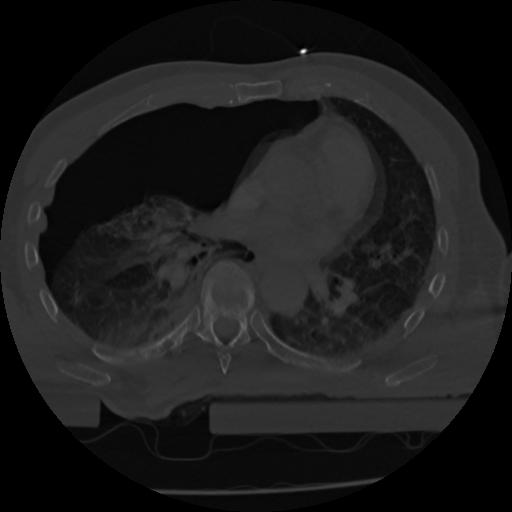

22 ANGIO,CE,Vol,0.5,ANGIO,,